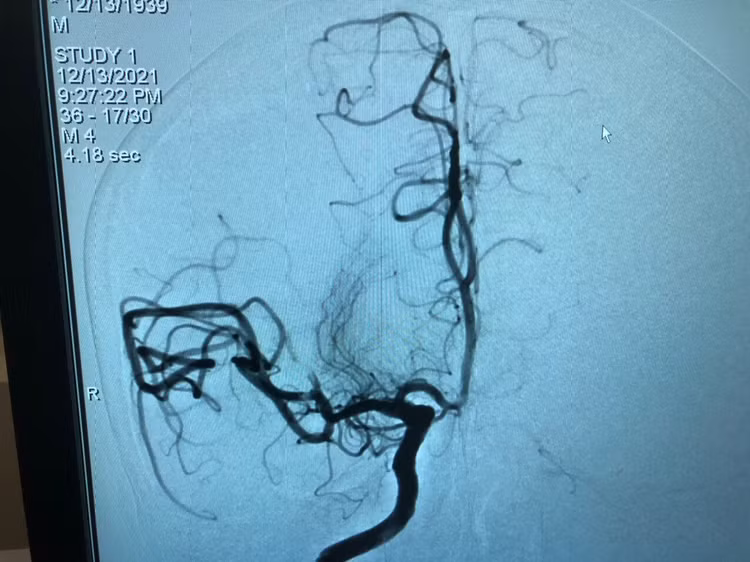

Bệnh nhân nữ (52 tuổi, Hà Nội) được đưa vào cấp cứu trong tình trạng thất ngôn, liệt mặt phải, yếu nửa người phải, cơ lực tay phải và chân phải 1/5, huyết áp 130/80mmHg. Chụp mạch não tắc động mạch não.

Người nhà cho biết, bệnh nhân có khám tại Bệnh viện E T.Ư, được chỉ định dùng sintrom (thuốc chống đông), 1 tuần nay bệnh nhân dừng thuốc. Khi phát hiện bệnh nhân nói khó, yếu nửa người phải, đưa vào viện được can thiệp lấy huyết khối và dùng thuốc tiêu sợi huyết. Sau can thiệp bệnh nhân được chuyển hồi sức điều trị và theo dõi tiếp.

Hút cục máu đông cho bệnh nhân đột quỵ tại Bệnh viện E T.Ư.